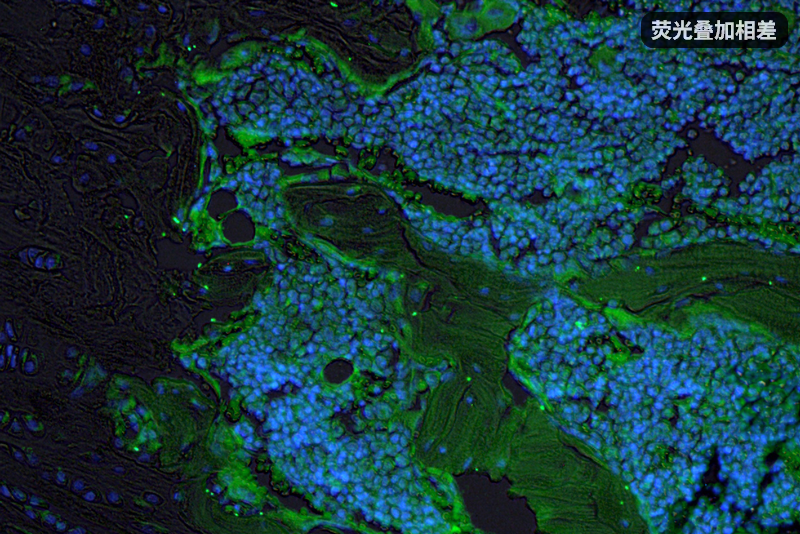

无限远倒置荧光显微镜合成图像

无限远光学显微镜可以做到相衬成像视野和荧光成像视野完全一致,因此可以拍摄合成出有轮廓感/立体感的细胞荧光图像。一般这需要先用平场消色差相衬物镜拍摄相衬,然后切换到半复消色差物镜拍摄荧光,以免损失荧光亮度,为了方便用户进行这种拍摄,明美还推出了半复消色差相衬物镜,可以一个物镜把相衬和荧光都拍好。